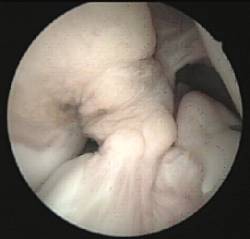

En aquells pacients immadurs amb inestabilitat anterior del genoll simptomàtica utilitzem la reconstrucció artroscòpica transepifisària amb tendó semitendinós del pacient.

S’evita el dany del cartílag de creixement mitjançant l’ús de tunelitzacions retrògrades (sistema de retroconstrucció) que ens permet restituir la funcionalitat de l’articulació sense afectar el cartílag de creixement i mantenint la isometria de l’empelt implantat.